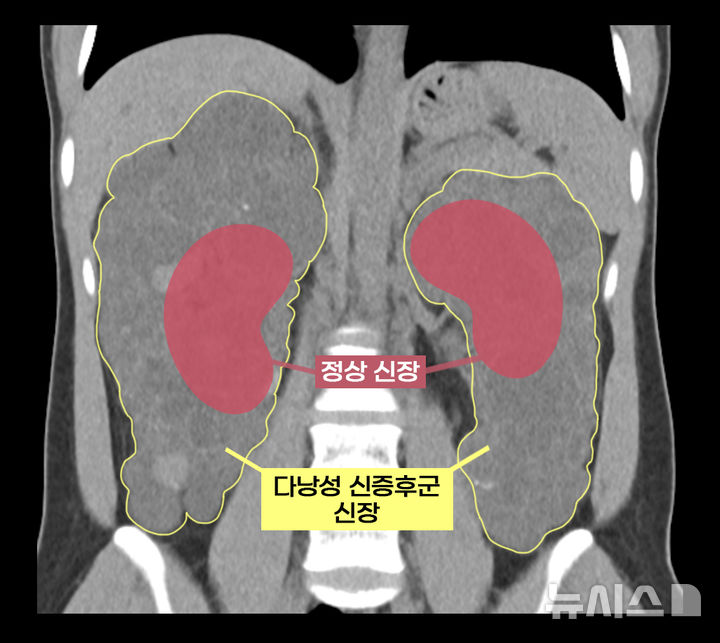

[서울=뉴시스]다낭성 신증후군 환자의 신장과 정상 신장 비교. (이미지= 서울아산병원 제공) 2025.06.30. [email protected].

이 씨는 상염색체 우성 다낭성 신증후군을 앓았다. 다낭성 신증후군은 신장에 셀 수없이 많은 낭종이 발생해 신장이 최대 축구공만큼 커지는 유전 질환이다. 1,000명 중 한 명꼴로 비교적 흔하게 발생하며 대부분 만성 신부전으로 이어진다.